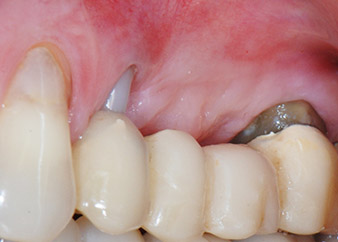

However, we maintained our initial plan to retain both teeth as temporary bridge abutments during the six-months osseointegration period of the implants. At reentry, the situation would have to be reassessed. First, in an attempt to manage the endo-perio problem, the remaining root surface was carefully debrided with piezoelectric equipment (Piezomed, W&H, used with the spatula-shaped insert S1, originally designed for erosion of the lateral sinus wall) (Fig. 4).

Then the apex was abraded with the same instrument to remove residual infected apical tissue and to reduce possible accessory root-canal ramifications (apicoectomy) (Fig. 5). A retrograde filling was not necessary because the orthograde filling had just been revised.